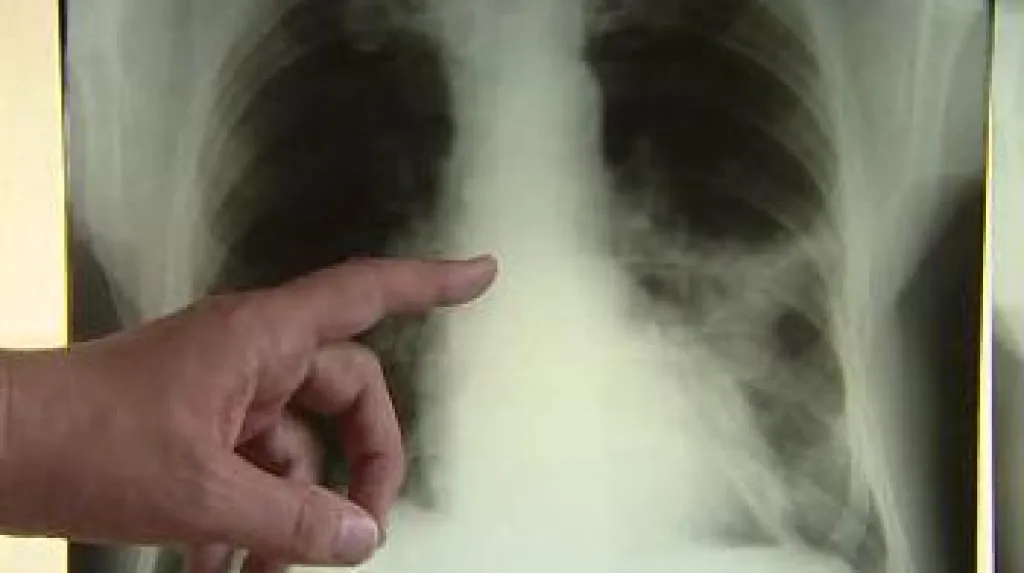

Pardubice - Hygienici nařídili vyšetřit desítky zaměstnanců pardubické firmy Foxconn. U čtyř pracovníků původem z Moldávie prokázaly lékařské testy tuberkulózu. Ve dvou případech se přitom jedná o otevřenou formu nemoci, což znamená i větší riziko pro okolí. Preventivní vyšetření teď musejí podstoupit všichni, kteří s nemocnými přišli do styku.

Mimořádná opatření hygienici nařídili poté, co testy prokázaly otevřenou formu tuberkulózy u dvou kmenových pracovníků firmy Foxconn. „V naší nemocnici byly vyšetřeny tři osoby a u jedné se diagnóza potvrdila. Tento pacient je hospitalizovaný v plicní léčebně v Humpolci,“ uvedla mluvčí Pardubické krajské nemocnice Ivana Faiklová. „Pacienta je třeba izolovat a okamžitě začít léčit,“ doplnil primář Oddělení plicních nemocí a tuberkulózy Vladimír Molnár.